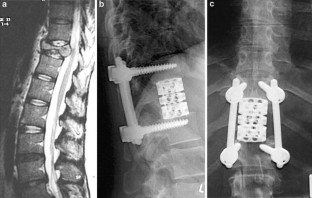

Introduction: The objectives of surgical interventions for tumoral lesions of the spine include the establishment and improvement of tumor-related symptoms. Anterior tumor resection followed by reconstruction indicated if surgical treatment allowed a marginal removal of the tumor or could extend the individual survival rate in combination with adjuvant therapy options. Sufficient re-stabilization depends on adequate anterior column reconstruction. The purpose of this retrospective study was to present our experiences and results after anterior tumor resection followed by reconstruction with the expandable vertebral body replacement device (VBR, Ulrich, Germany) based on clinical application over 4°years. Patients and methods: We carried out an anterior tumor resection followed by reconstruction using an anterior extendable device in 32 patients with different spine tumors between 1996 and 2000. A retrospective evaluation was executed considering the patients medical records and radiological findings. Additionally, a clinical and radiological investigation of still living postoperative patients was carried out. Results: The mean surgical time of all evaluated patients was 317.2 min. The average blood loss was 1,272.5 ml. According to the Tokuhashi score, patients with a postoperative survival time of at least 12 months demonstrated a score value ≥9 points. According to our evaluated patients group metastatic lesions of the spine represented the largest group (78.1%). The average survival rate of this group amounted to 18.4 months postoperatively. Considering primary tumors the average survival rate at the time of last re-examination amounted to 34.8 months postoperatively. Preoperative neurological pathologies were present in 12 patients (Frankel stage C--D). During the postoperative monitoring period 58.3% of the patients demonstrated an improvement in initial neurological findings. There were no intraoperative complications or perioperative deaths. Implant dislocations were not observed. Conclusion: On account of the underlying, the anterior tumor resection with supplementary instrumentation represented a sufficient procedure in spinal tumor surgery. Adjuvant therapy can influence the postoperative survival period positively in addition to the surgical procedure. Following anterior tumor resection, extendable vertebral body replacements like the VBR device provide immediate spine stability by excellent defect adaptation. With regard to their intraoperative flexibility, expandable cages are more advantageous in contrast to non-expandable implants or bone grafts.